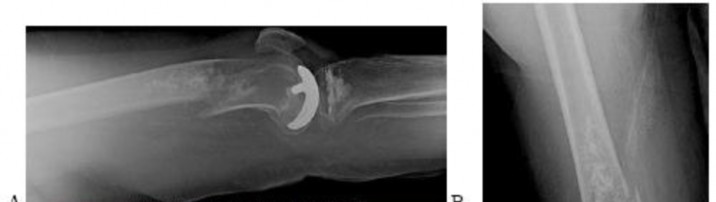

A 15-year-old male presents with deep knee pain awakening him at night. Radiographs show a permeative destructive lesion in the distal femoral metaphysis with a 'sunburst' periosteal reaction and Codman's triangle.

Biopsy confirms high-grade conventional osteosarcoma. What is the most critical prognostic factor for long-term overall survival in this patient?